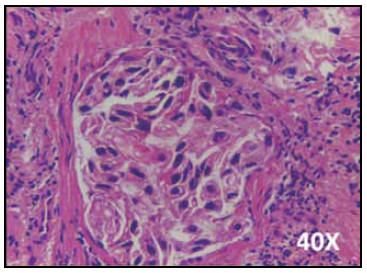

Ante los hallazgos identificados en las imágenes previas, se hicieron estudios de extensión para identificar foco neoplásico primario, la TAC contrastada de abdomen no mostró lesiones sugestivas de primario y la TAC contrastada de tórax (Figura 2) evidenció una masa pulmonar espiculada sin cavitación en el lóbulo superior derecho, adenopatías de localización hiliar derecha de 15 mm de diámetro en el eje corto y paratraqueales derechas de 13 mm de diámetro en el eje corto, sin lesiones líticas o blásticas en las estructuras óseas. La lesión pulmonar era sugestiva de carcinoma broncogénico siendo necesaria su confirmación histológica por biopsia mediante fibrobroncoscopia. Los hallazgos de la biopsia confirmaron el diagnóstico de un carcinoma de célula no pequeña compatible morfológicamente con un adenocarcinoma broncogénico (Figura 3), los marcadores de inmunohistoquímica fueron positivo para TTF1 (Figura 4) y negativo para P63 (Figura 5).

Figura 3 Tinción hematoxilina-eosina de biopsia pulmonar. Técnica microscopía de luz. Coloración hematoxilina-eosina. Aumento 40x. Se observa infiltración por estructuras neoplásicas de aspecto glandular tapizadas por células de núcleos pleomórficos, algunas con nucléolos de citoplasma amplio eosinófilo. Los hallazgos son compatibles morfológicamente con un adenocarcinoma broncogénico.